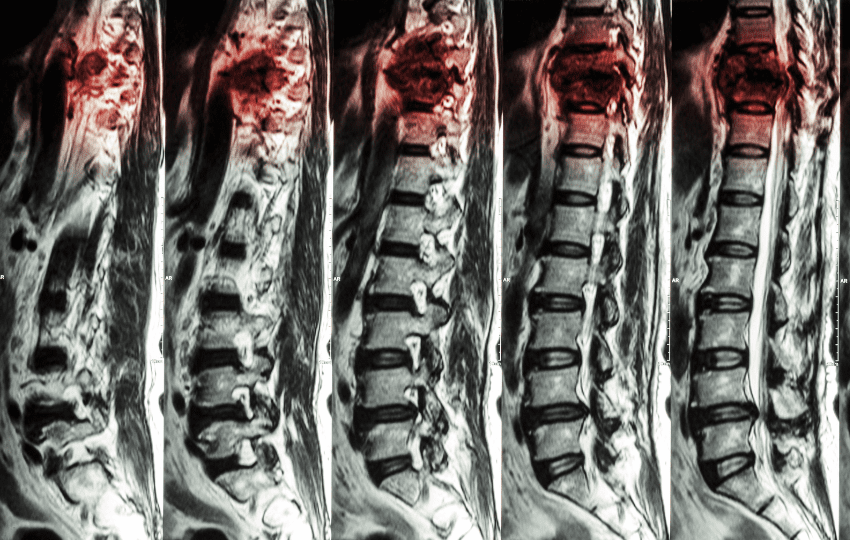

O choque neurogênico ocorre principalmente como consequência de lesão aguda da medula espinhal, especialmente em níveis cervicais ou torácicos altos. É mais comum em lesões nas vértebras cervicais e torácicas superiores, acima do nível de T6.

Outras causas menos comuns incluem lesões cerebrais graves, anestesia raquidiana ou bloqueios neurais extensos, mas, no contexto clínico, a lesão medular traumática é de longe a etiologia predominante.

- Principais causas traumáticas primárias: acidentes de carro, quedas, mergulhos, ferimentos por arma de fogo, e fraturas e luxações durante esportes.

- Lesões secundárias: ocorrem posteriormente ao trauma, secundárias a hemorragia, isquemia, inflamação etc.